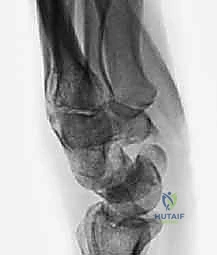

- الأشعة السينية الرقمية (Digital X-rays): بأوضاع متعددة (AP, Lateral, Scaphoid view) لتقييم زوايا العظام ودرجة الانهيار.

- الأشعة المقطعية (CT Scan): وهي المعيار الذهبي لتقييم حجم العظم المتآكل بدقة ثلاثية الأبعاد، وتحديد مدى الخشونة في المفاصل المحيطة.

- الرنين المغناطيسي (MRI): لتقييم حيوية العظم (هل العظم ميت أم حي؟) وفحص الأربطة المحيطة.